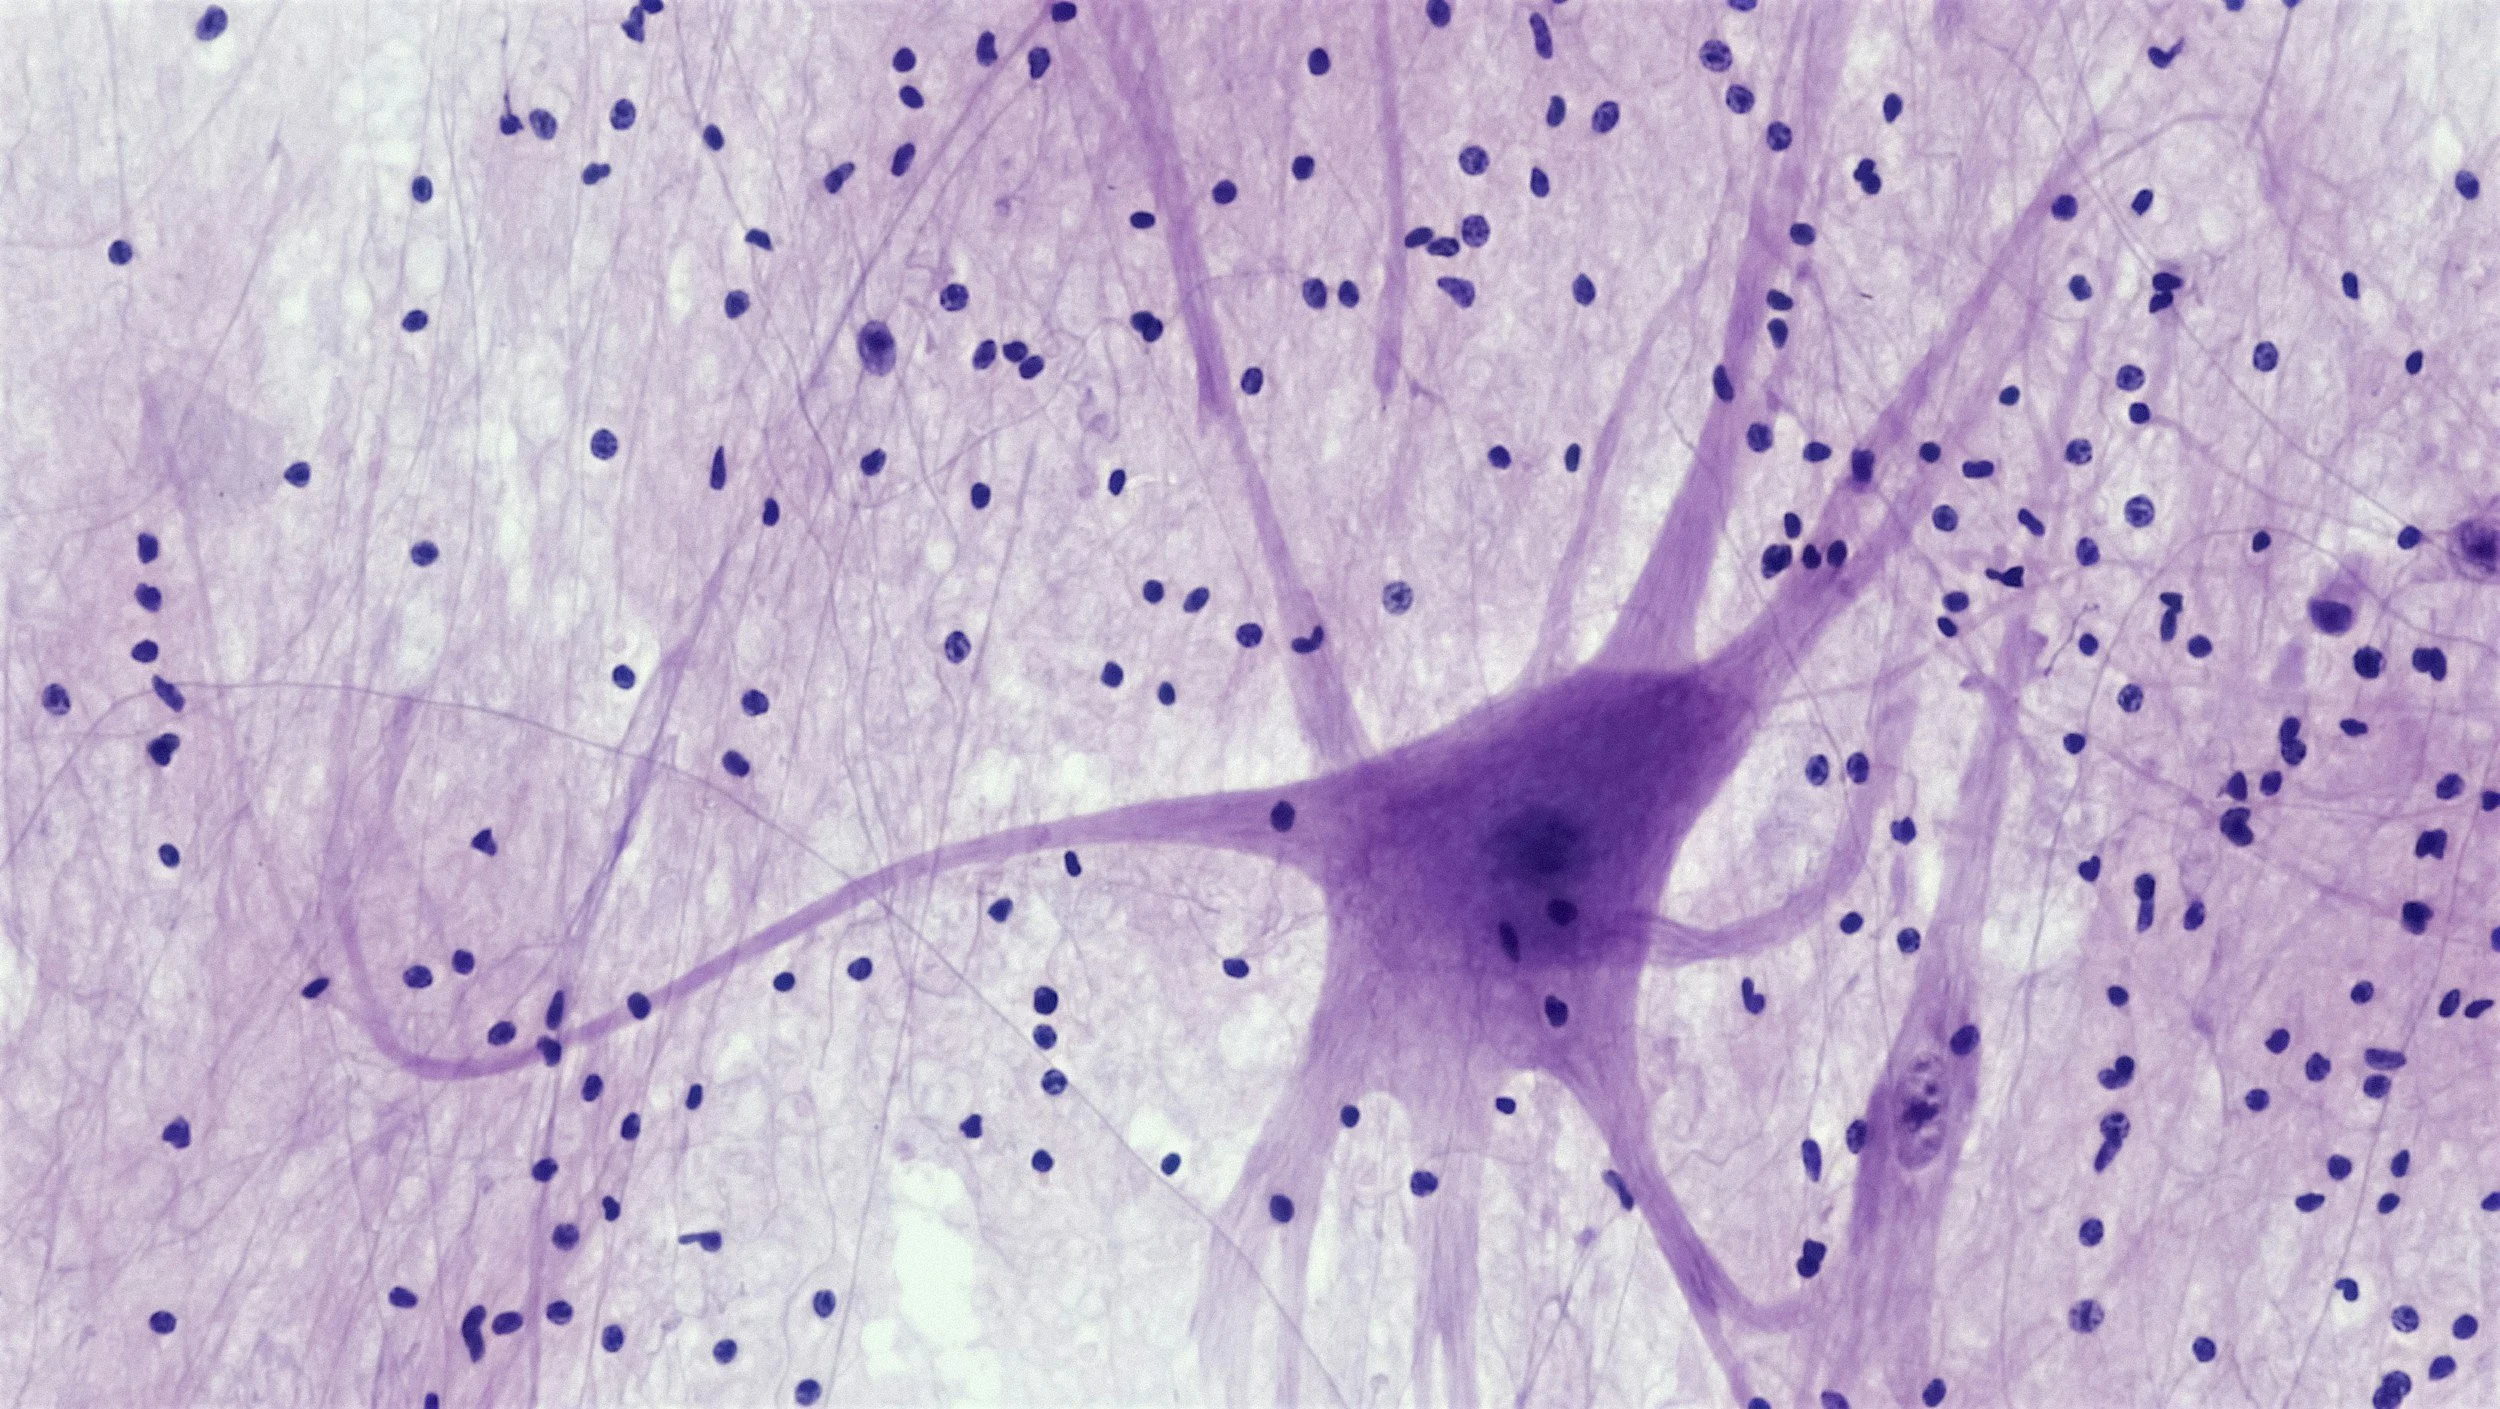

Microscopic view of neurons with purple cell bodies and numerous surrounding dark blue nuclei.